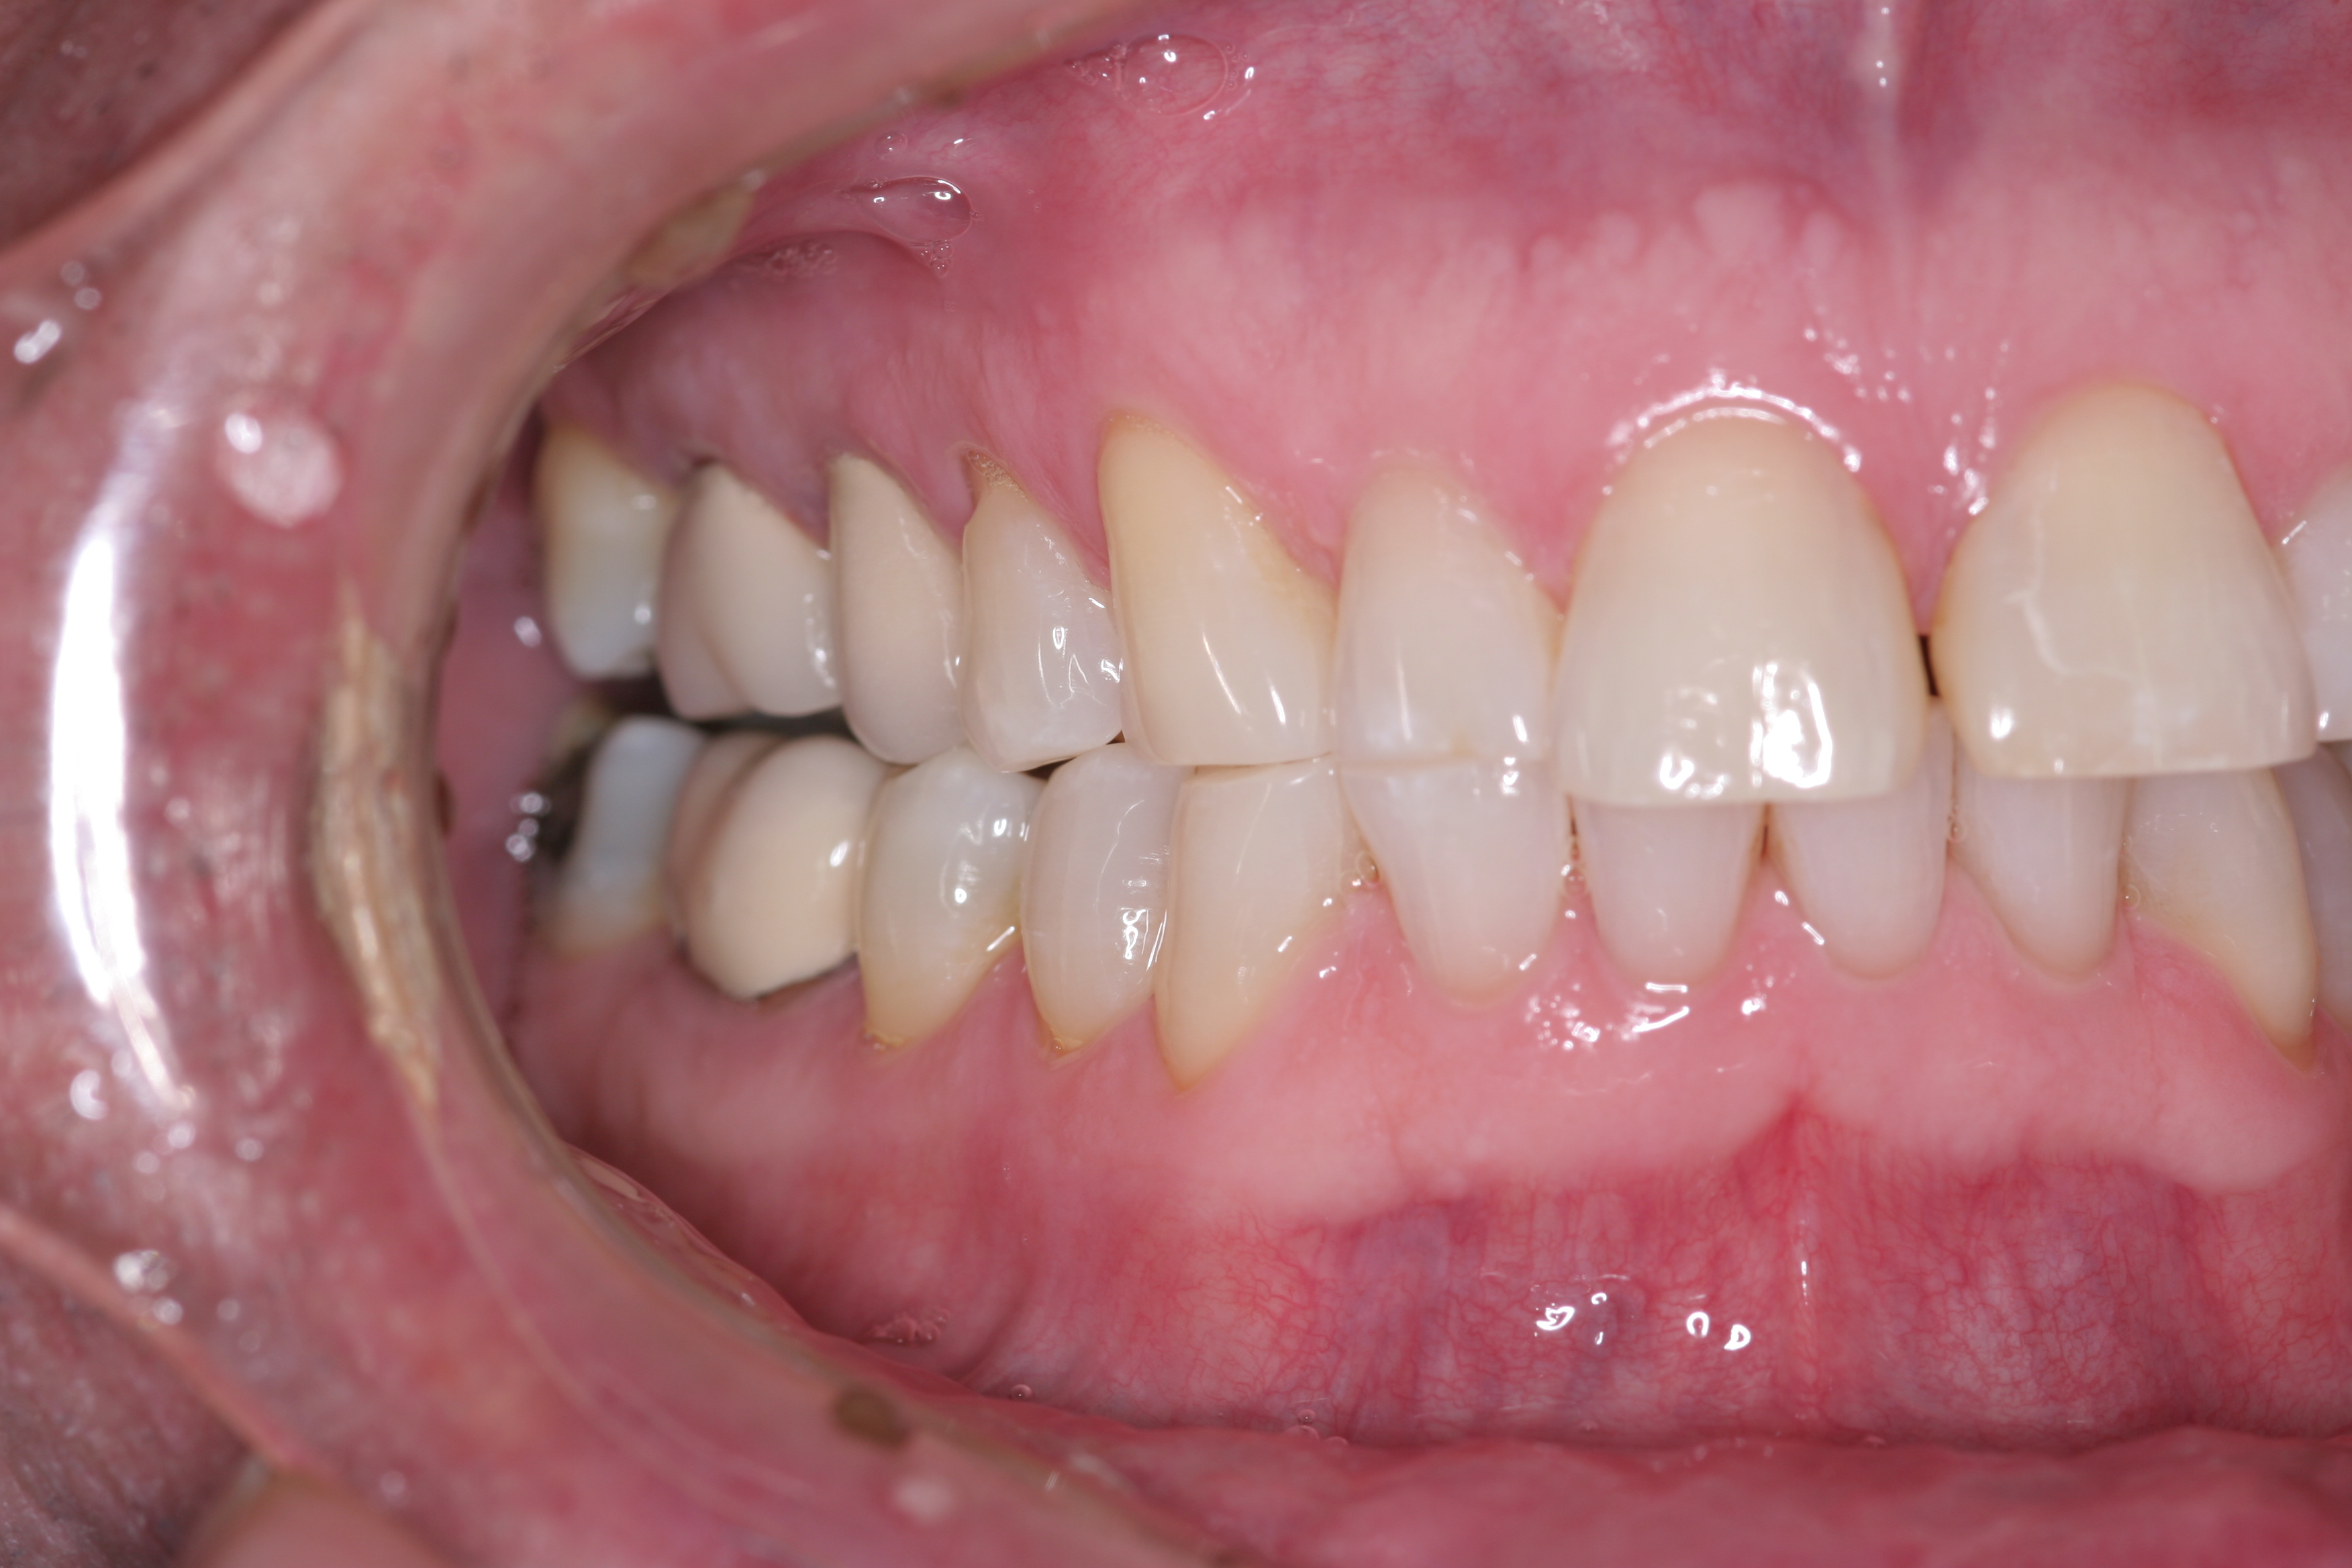

(11.) A patient presented with advanced generalized wear of her anterior teeth, and was displeased with their overall appearance because of their color and wear.

Figure 11

(12.) A patient presented with advanced generalized wear of her anterior teeth, and was displeased with their overall appearance because of their color and wear.

Figure 12

A patient presented with advanced generalized wear of her anterior teeth (Figure 10 and Figure 11). She was displeased with their overall appearance because of their color and wear (Figure 12). A complete examination was performed, revealing instability in her temporomandibular lateral poles bilaterally, sore muscles of mastication, advanced wear, a CR/MIP discrepancy, and loss of her anterior guidance due to the wear. Although the topic is beyond the scope of this article, the patient was also screened for possible sleep apnea. This included an evaluation of the Mallampati score, previous sleep therapy evaluation or treatment, snoring history, an evaluation of her neck size, her weight status, and the presence of the tonsils and their size. In every case, if this clinician suspects airway obstruction to be playing a role in tooth wear issues, the patient is referred to a sleep physician. The patient in this case displayed few apnea risk factors, and the patient’s anterior wear facets fit together like a “lock and key” pattern seen in parafunctional activity. Splint therapy was initiated to stabilize the joints and muscles. A repeatable CR position was verified through load testing. At this point diagnostic models, photographs, a CR bite record, and a facebow were taken and recorded.